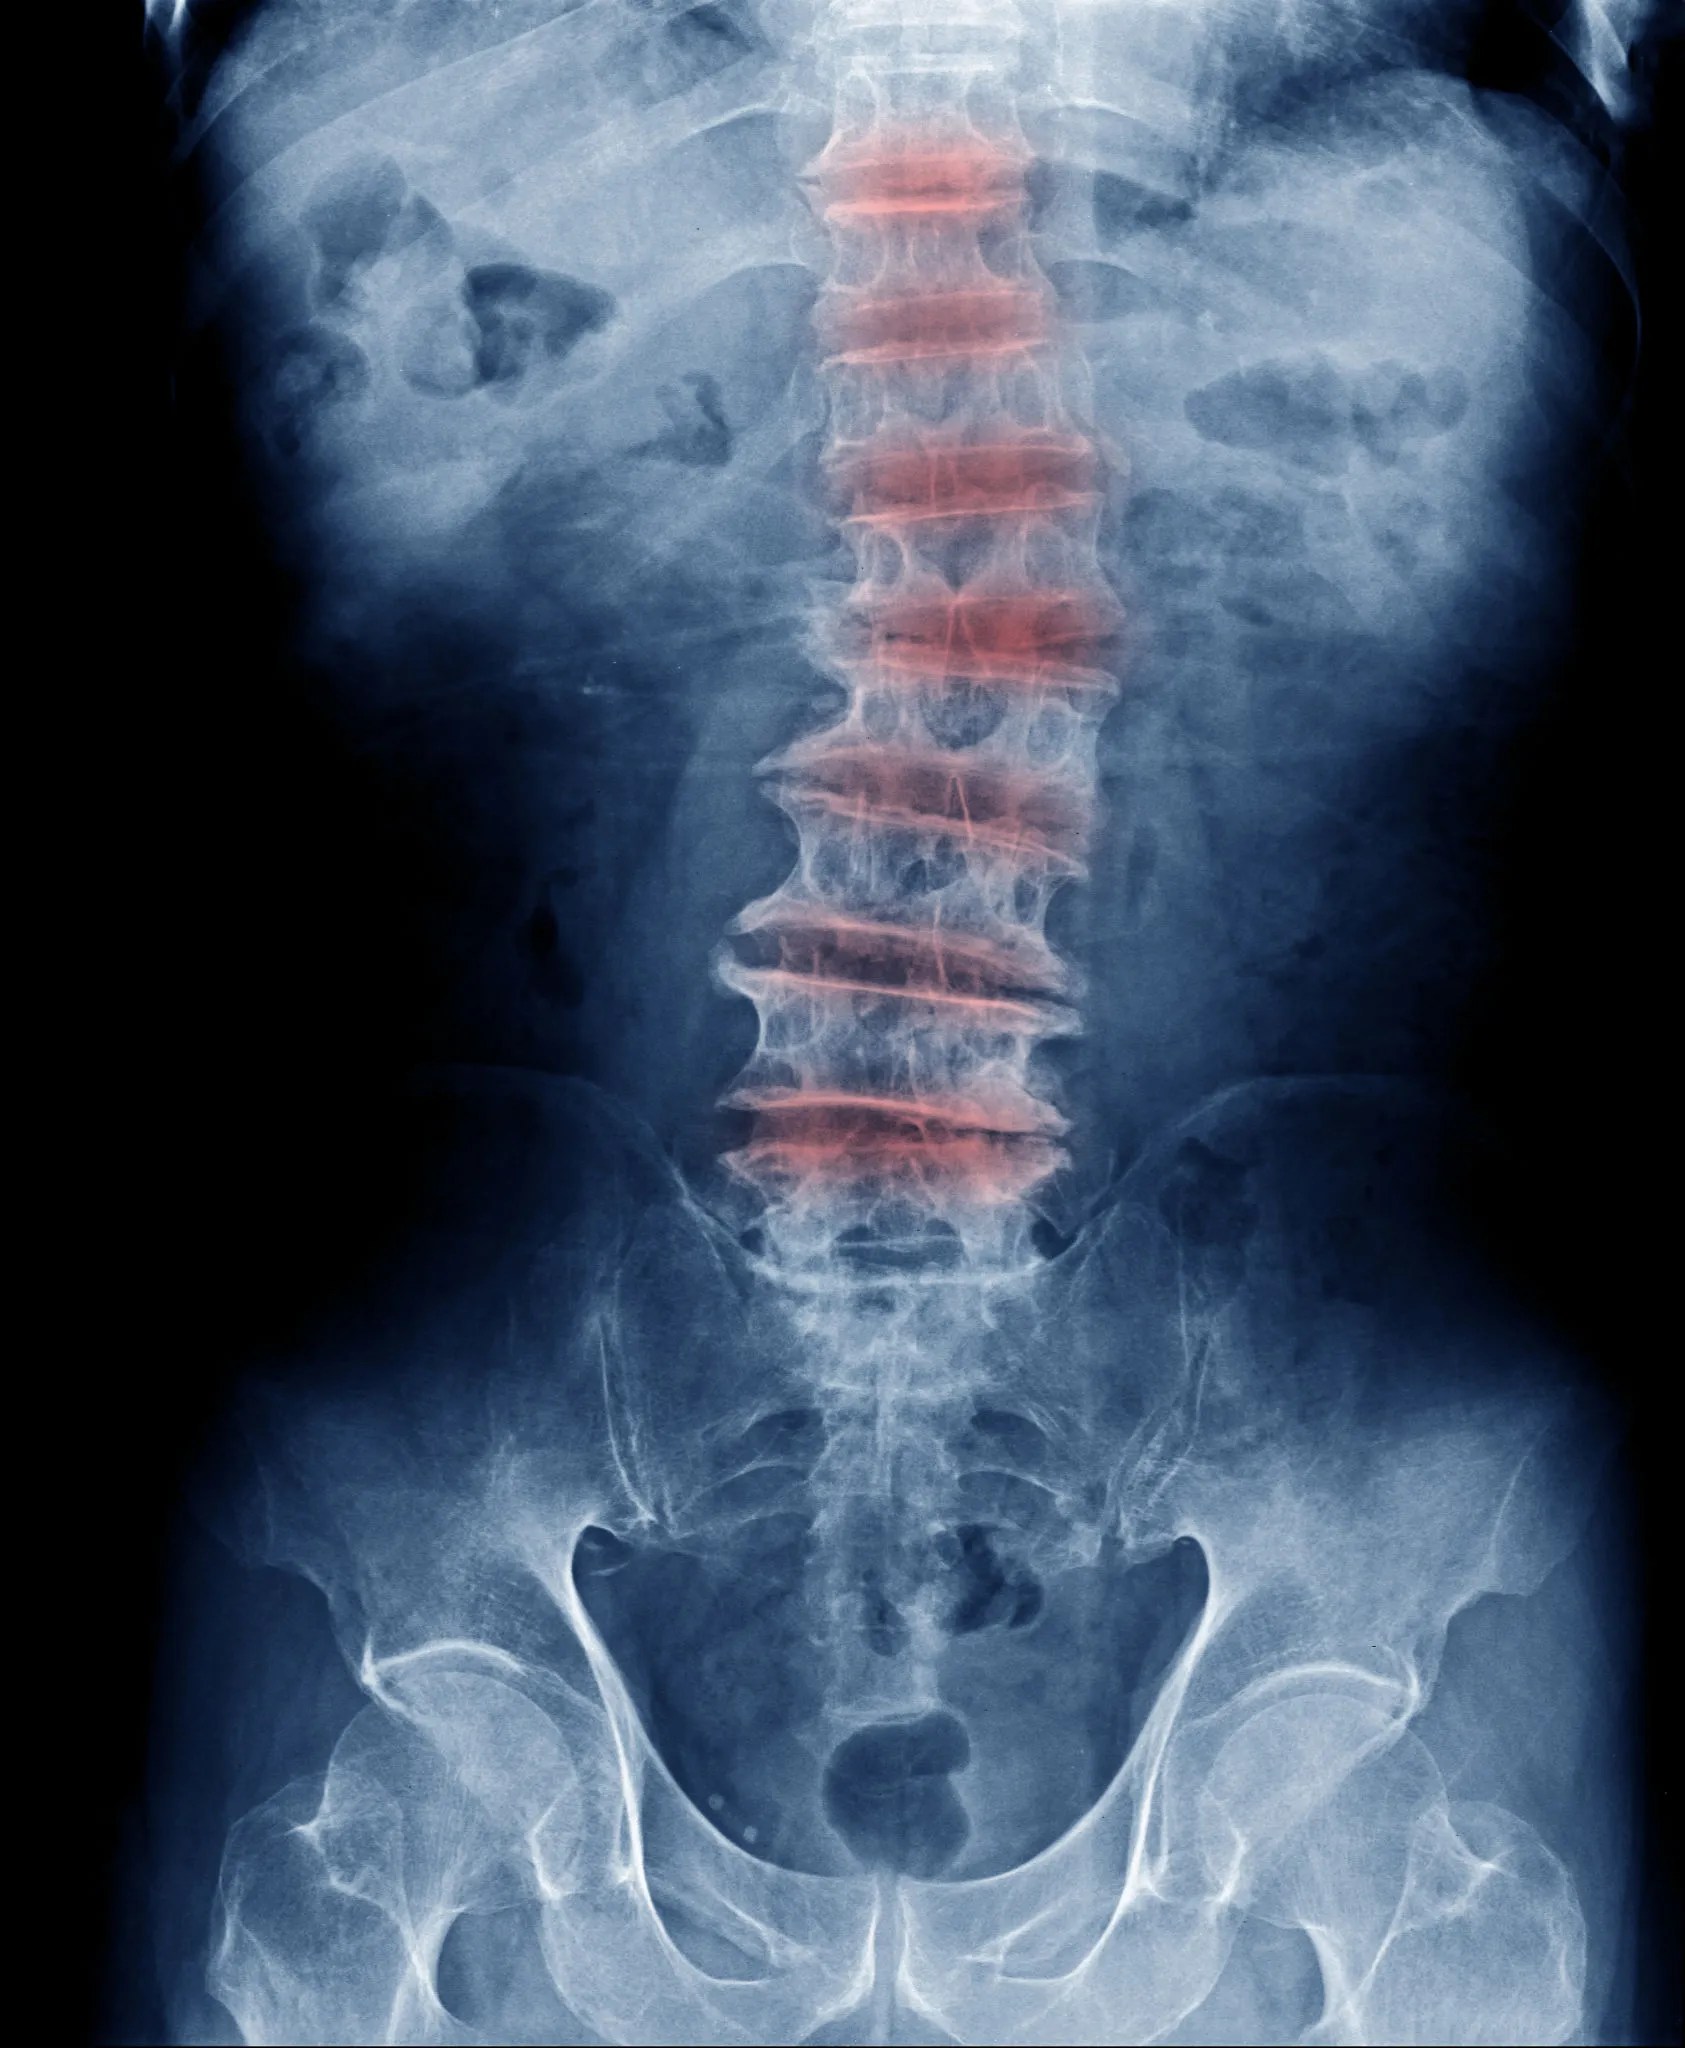

Chiropractor For Degenerative Disc Disease Near Me . Disc degeneration causes pain and difficulty moving because the bones of the spine get in the way of nerves. Chiropractic care can relieve spinal pain and tension, and improve the flexibility of the spine, helping our patients manage degenerative disc disease. The team at delaware integrative medicine has years of experience treating a wide range of conditions, including degenerative disc disease. Chiropractic care for disc degeneration disorder includes applying techniques. Can a chiropractor make degenerative disc disease worse? This question has been asked by some people who are not clear about what chiropractors actually do, and are afraid that spinal manipulations might end up worsening the situation for someone bothered by degenerative disc disease (ddd). Chiropractic care is a treatment option you may want to try for degenerative disc disease (ddd). How chiropractic care can help relieve degenerative disc disease. The first step the chiropractor will take with ddd is to carefully determine if you. What will our physicians do to treat a case of ddd? Chiropractic care is gaining prominence as a conservative approach to address degenerative disc disease, prioritizing. When considering chiropractic care for degenerative disc disease, it’s essential to find a qualified and experienced chiropractor.

Chiropractic care is a treatment option you may want to try for degenerative disc disease (ddd). Can a chiropractor make degenerative disc disease worse? This question has been asked by some people who are not clear about what chiropractors actually do, and are afraid that spinal manipulations might end up worsening the situation for someone bothered by degenerative disc disease (ddd). When considering chiropractic care for degenerative disc disease, it’s essential to find a qualified and experienced chiropractor. How chiropractic care can help relieve degenerative disc disease. Chiropractic care for disc degeneration disorder includes applying techniques. The first step the chiropractor will take with ddd is to carefully determine if you. Chiropractic care can relieve spinal pain and tension, and improve the flexibility of the spine, helping our patients manage degenerative disc disease. Disc degeneration causes pain and difficulty moving because the bones of the spine get in the way of nerves. What will our physicians do to treat a case of ddd?